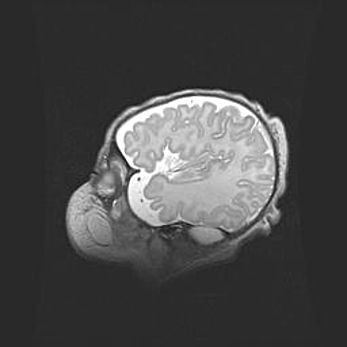

Мальформация Денди-Уокера. Киста задней черепной ямки.

Агенезия мозолистого тела.

Возраст: 2,5 месяца

Вес: 2420 г

Пол: женский

Окружность головы: 37 см

Срок гестации: 32 недели

Мальформация Денди—Уокера — редкий вид патологии ЦНС, представляющий собой врожденный порок развития каудального отдела ствола и червя мозжечка, ведущий к неполному раскрытию срединной (Мажанди) и латеральных (Лушка) апертур IV желудочка мозга. Для этогно синдрома характерна триада симптомов: гипотрофия червя мозжечка и/или полушарий мозжечка, кисты задней черепной ямки, гидроцефалия различной степени. В 70% случаев порок сочетается и с другими аномалиями головного мозга, в частности с агенезией мозолистого тела.